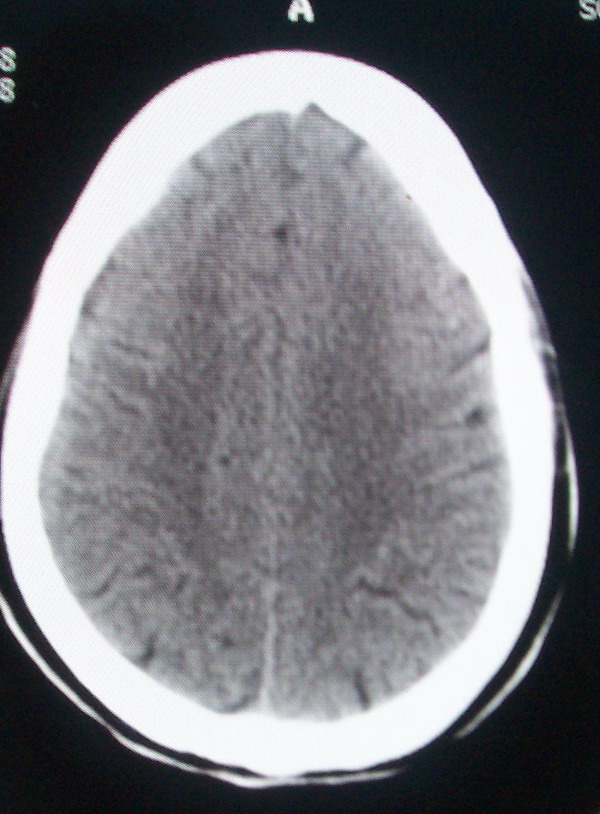

标题: CT13599:大家看是正常还是软化灶?已经重新上传 [打印本页]

标题: CT13599:大家看是正常还是软化灶?已经重新上传

考虑正常.最好有连续层面.

所给图片未见异常。

正常脑沟。

正常。